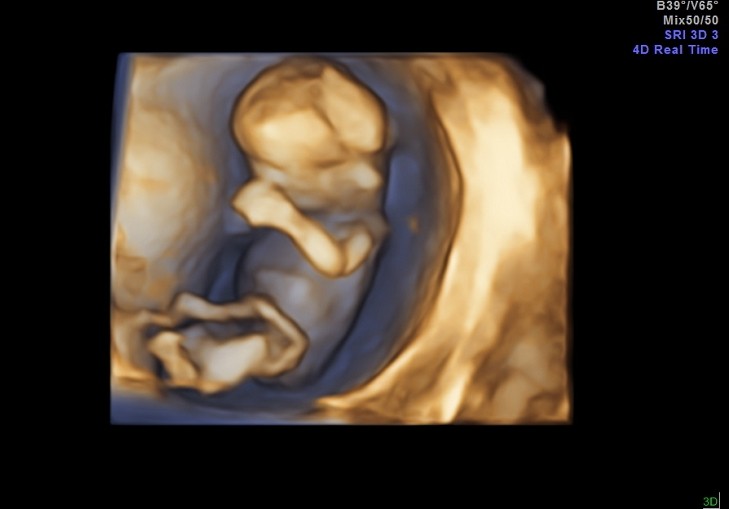

Ale najważniejsze - Dzidzia ma prawie 5 cm, wierciła sie i skakała jak oszalała, wierzgała rączkami i nóżkami